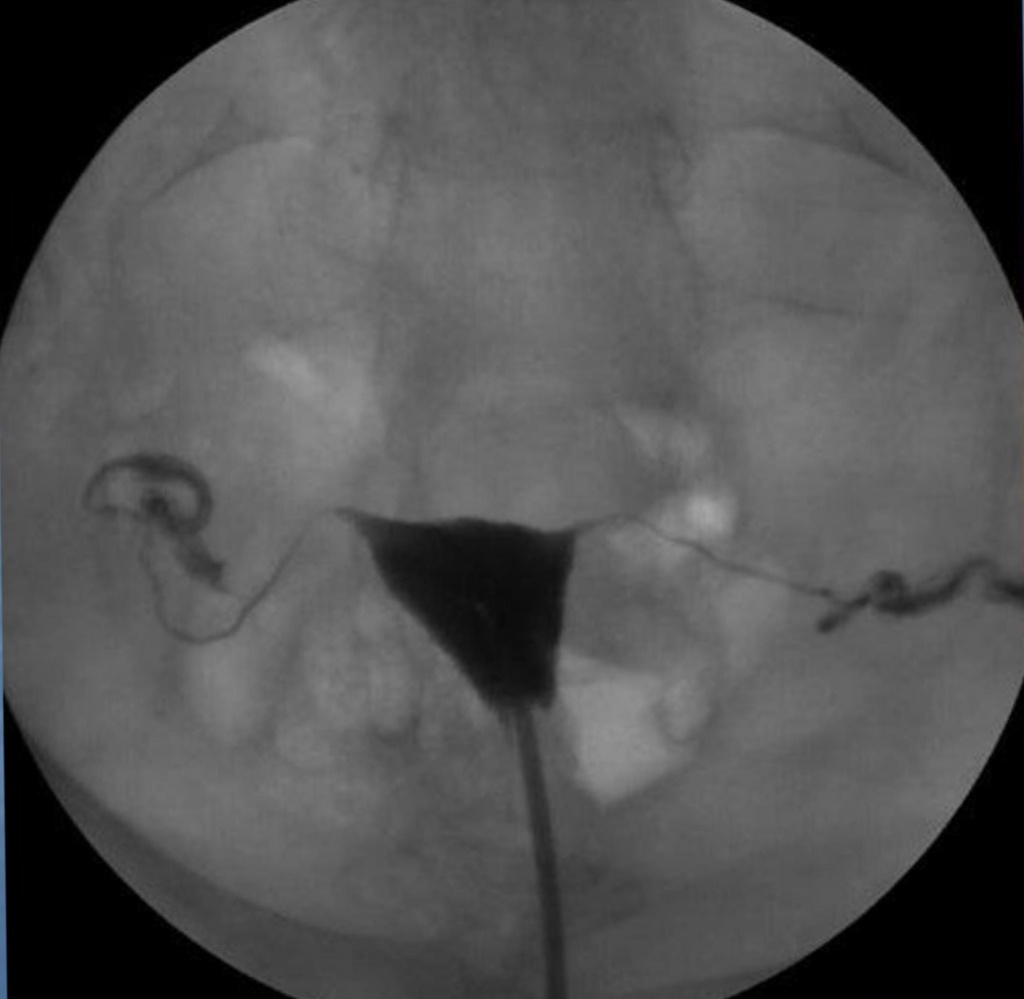

Гистеросальпингография: описание и фотографии